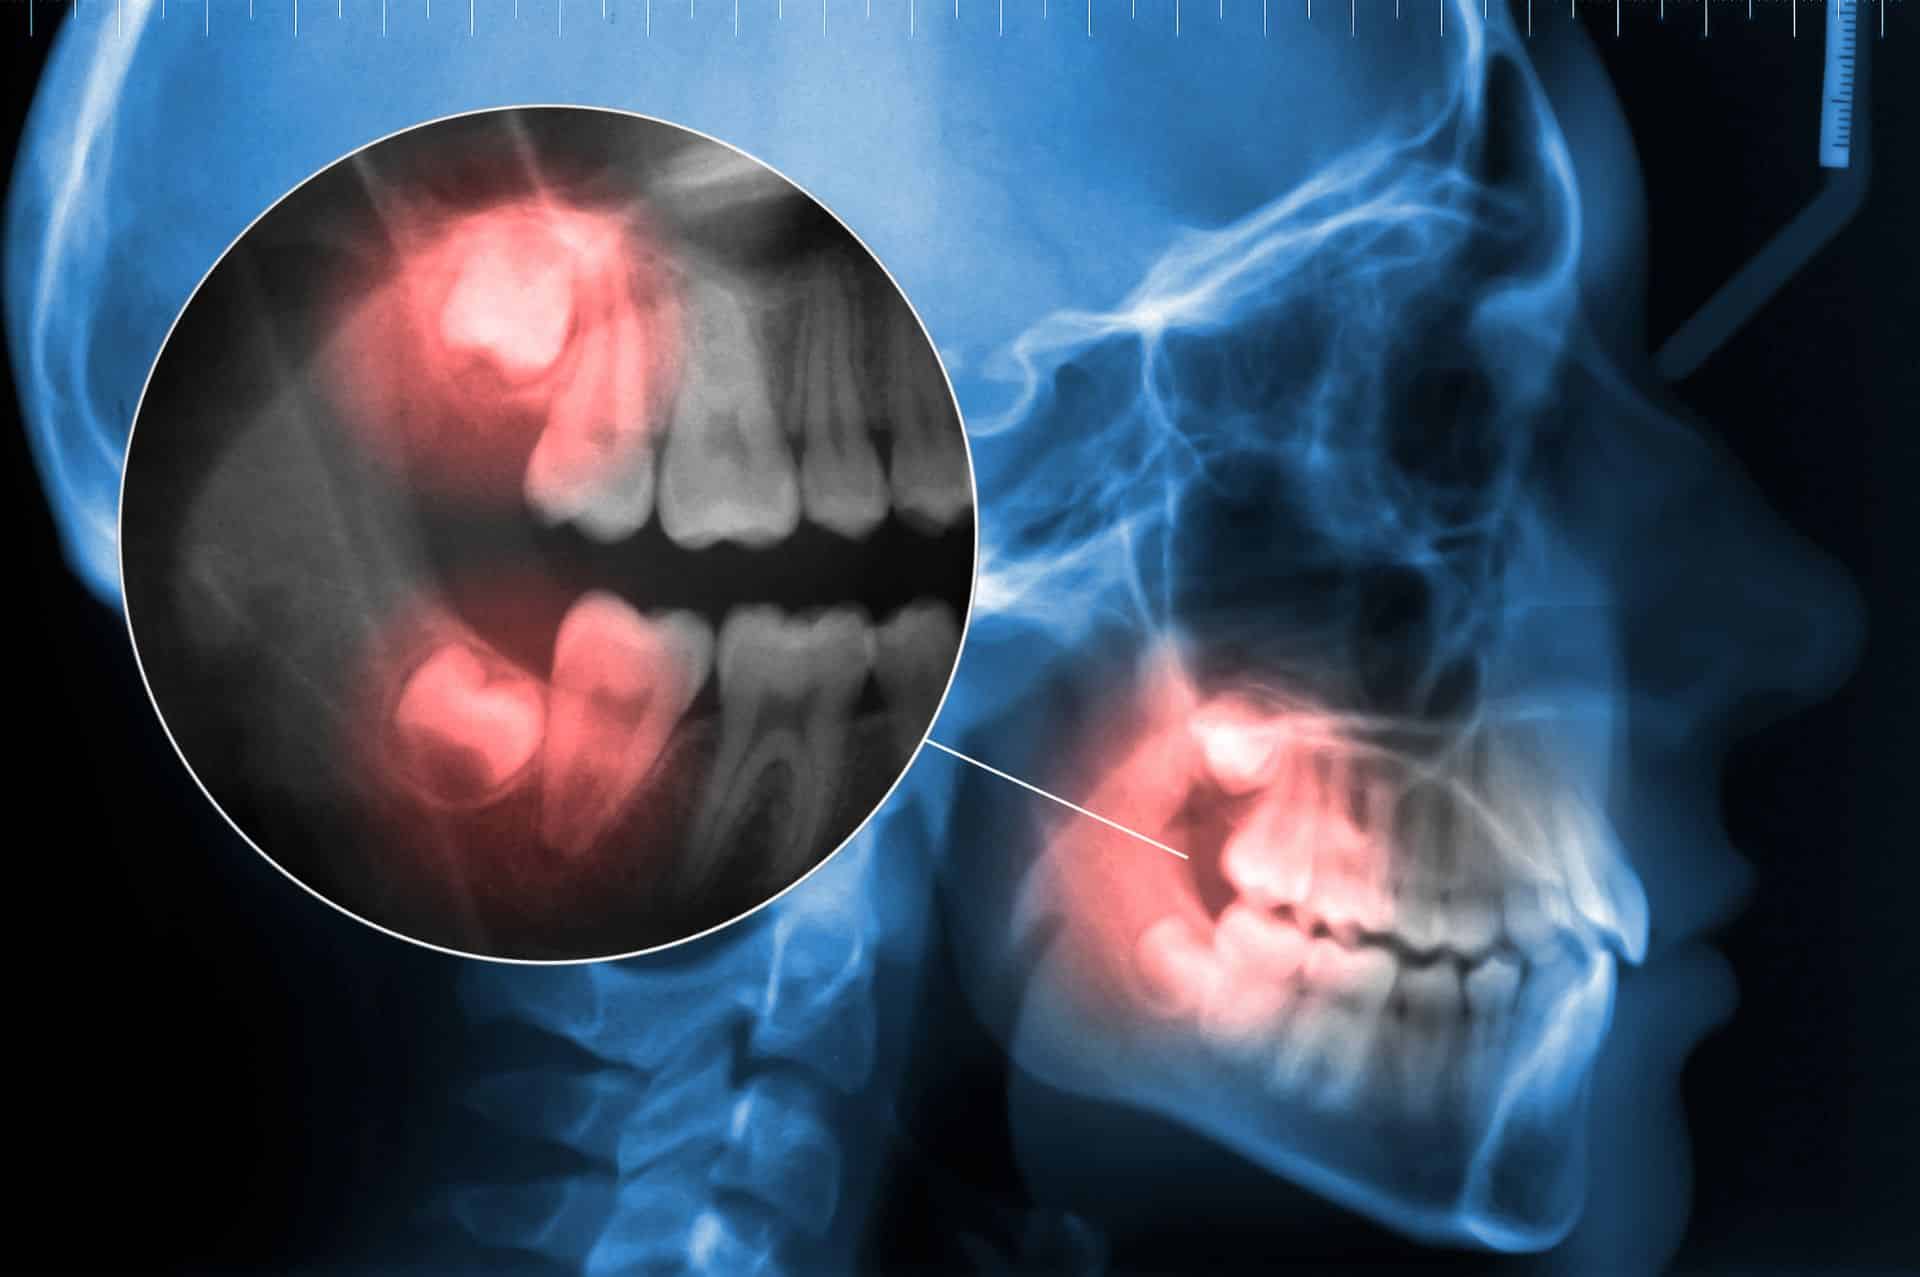

Οι ιδιαιτερότητες της ανατομίας, όπως:

Η πορεία του κάτω φατνιακού νεύρου

Η εγγύτητα με το ιγμόρειο άντρο (σε άνω φρονιμίτες)

Το επίπεδο έγκλεισης του δοντιού